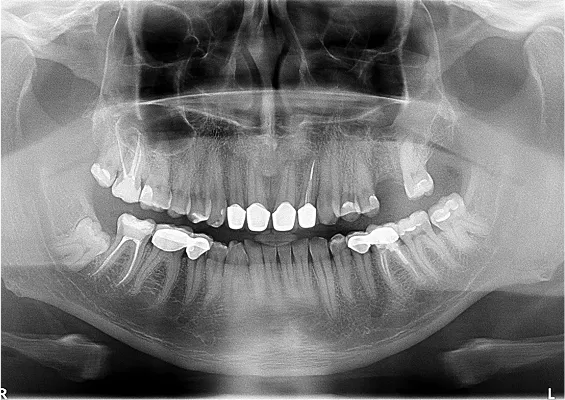

ODBUDOWA UBYTKU PO USUNIĘCIU ZĘBA - SOCKET PRESERVATION

To prosta, szybka i bezpieczna technika odbudowy kostnej zębodołu po ekstra-kcji zęba. Znana wcześniej, lecz opisana dopiero w ramach międzynarodowego konsensusu z 2010 roku (prof. Lindhe, prof. Araujo)

Zabieg odbudowy zębodołu powinno się wykonać możliwe jak najszybciej po usunięciu zęba. Jego celem jest odbudowa naturalnej objętości kości w miejscu utraconego zęba, a następnie szybkie wprowadzenie implantu. Najlepsze rezul-taty uzyskuje się przy zastosowaniu biomateriału w formie bloczków kolageno-wych lub granulatu, które dają trwałe efekty odbudowy oraz optymalną funkcję i estetykę odtworzonych koron zębów na wszczepionym implancie.